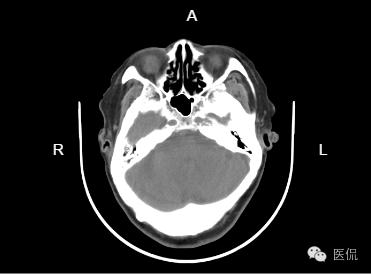

病例二

患者信息:女,80岁

检查部位:h

检查方法:平扫

患者主诉:两年前CT显示,梗塞,现正常体检

影像所见:

左侧基底节区及左脑干区见小斑片状低密度灶,部分边界欠清;侧脑室旁脑白质对称性减低,余双侧大脑组织内未见异常密度,脑干及小脑形态、大小正常,内未见异,中线居中,各脑室及脑池增大、脑皮层沟回加深加宽,余未见异常。骨窗下诸颅骨无明显异常。

诊断意见:

1、左侧基底节区及左脑干腔隙性脑梗塞。建议结合临床随访复查!

2、脑白质疏松;

3、老年性脑萎缩。